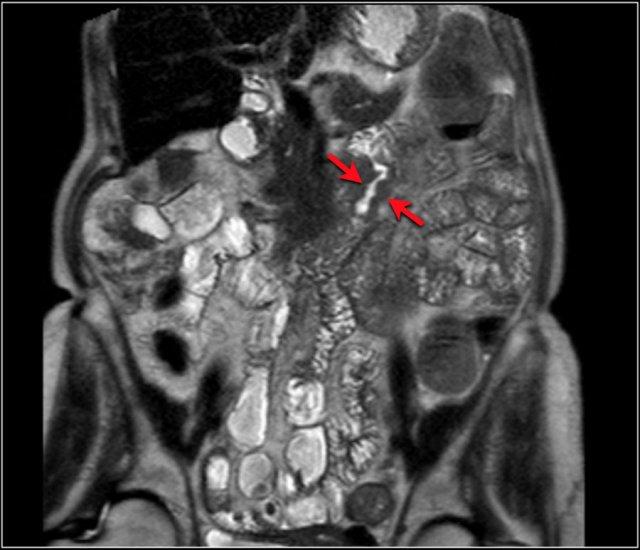

Chuỗi xung T1W sau tiêm thuốc tương phản từ có fat-sat (trái) và chuỗi xung T2W (phải) cho thấy một khối gây tắc nghẽn ở hỗng tràng với bờ dạng vai (mũi tên).

Có giãn ruột trước chỗ hẹp.

Đây là ung thư biểu mô tuyến ở đoạn gần hỗng tràng.

Khối u được hiển thị rõ hơn trên MRI so với CT.